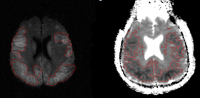

3D Segmentations of Anatomic Structures and Ischemic Lesions in Brain

Brain Volume

Core Infarct Volume

Volumetry of Bilateral Cortical Ischemiaon DWI (left) and ADC (right)

Filippi CG, El-Ali AM, Chow DS, Miloushev VZ, Guo X, Zhao B, Computer-assisted Volumetric Measurement of Core Infarct Volume in Pediatric Patients: Feasibility for Clinical Use and Development of Quantitative Metrics for Outcome Prediction, AJNR Am J Neuroradiol. 2015; 36(4):789-94.

De Marchis GM, Filippi CG, Guo X, Pugin D, Gaffney CD, Dangayach N, Suwatcharangkoon S, Falo MC, Schmidt JM, Agarwal S, Connolly ES Jr., Claassen Jan, Zhao B, Mayer SA. Brain Injury Visible on Early MRI after Subarachnoid Hemorrhage Might Predict Neurological Impairment and Functional Outcome. Neurocrit Care. 2015; 22(1):74-81.